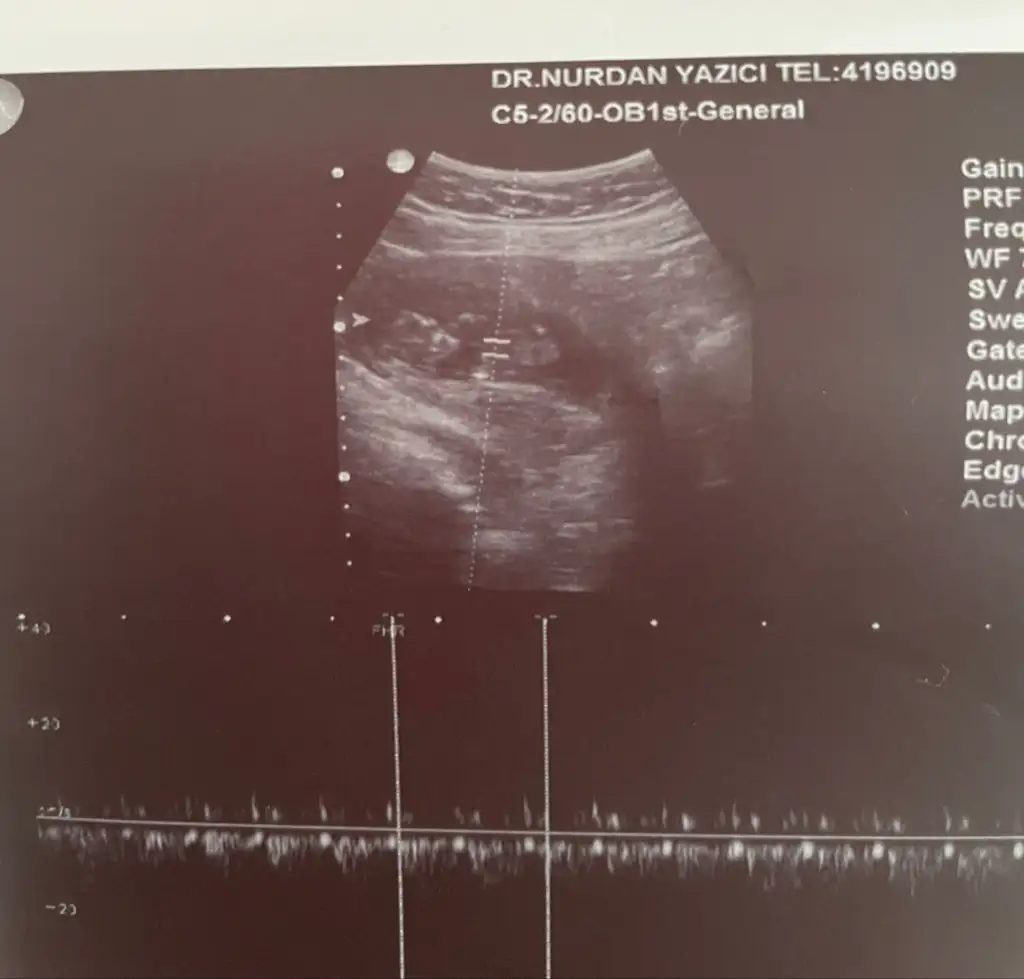

Kese fasülye şeklinde cinsiyet tahmini yapabilir miyiz

Kızlar cinsiyet tahmini yapabilecek var mı

Amin inşallah 🙏 sağolun 25 haftaligim halada doktor kesin birşey demiyor yüzde 90 kız ama bir cikinti var diyor bacak arası fotoğraflari bu sekilde